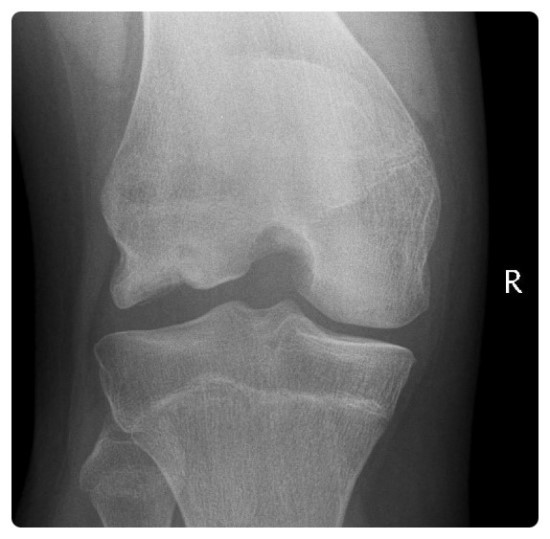

△ 박리성 골연골염의 단순 방사선 촬영 소견

우측 대퇴골 외과의 괴사부위가 과간 절흔상(intercondylar notch view)에서 관찰된다.